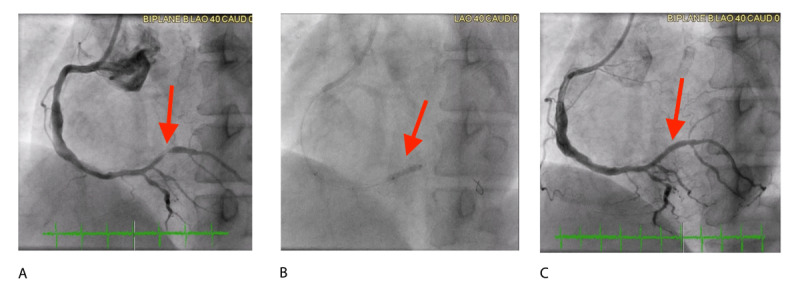

从1929年第一次心脏导管置入到药物包覆球囊(DCBs)作为支架内再狭窄(ISR)的治疗手段,导管介入的发展彻底改变了冠状动脉疾病(CAD)的治疗。这篇综述探讨了dcb在CAD中的发展和临床应用,特别关注它们在处理ISR、新发冠状动脉疾病和复杂病变中的作用。dcb将抗增殖药物(如紫杉醇或西罗莫司)输送到血管壁,并已成为传统支架治疗的一种有希望的替代方案,减少了对永久性金属植入物的需求和相关的血栓形成风险。早期的研究证实了dcb在ISR中的有效性,最近的研究将其应用范围扩大到小血管疾病、分叉病变和长弥漫性病变。值得注意的是,在某些情况下,DCBs显示出药物洗脱支架的非劣效性,包括高风险患者和冠状动脉解剖结构复杂的患者。尽管存在一些挑战,如潜在的冠状动脉夹层和需要最佳的病变准备,但DCBs在减少再狭窄和改善各种患者群体的长期预后方面显示出强大的潜力。虽然需要进一步的研究来完善其在标签外适应症中的应用,但dcb可能是CAD管理中通用、有效和更安全的方法。

The development of catheter-based interventions has revolutionized the treatment of coronary artery disease (CAD), from the first heart catheterization in 1929 to the emergence of drug-coated balloons (DCBs) as a treatment for in-stent restenosis (ISR). This review explores the evolution and clinical application of DCBs in CAD, with a particular focus on their role in managing ISR, de novo coronary disease, and complex lesions. DCBs deliver antiproliferative drugs such as paclitaxel or sirolimus to the vessel wall and have emerged as a promising alternative to traditional stent-based therapies, reducing the need for permanent metallic implants and associated thrombotic risks. Early research demonstrated the effectiveness of DCBs in ISR, and recent studies have expanded their application to small vessel disease, bifurcation lesions, and long diffuse lesions. Notably, DCBs have shown non-inferiority to drug-eluting stents in certain cases, including high-risk patients and those with complex coronary anatomy. Despite some challenges, such as the potential for coronary dissection and the need for optimal lesion preparation, DCBs have demonstrated strong potential in reducing restenosis and improving long-term outcomes in a variety of patient populations. While further studies are required to refine their use in off-label indications, DCBs may represent a versatile, effective, and safer approach in the management of CAD.